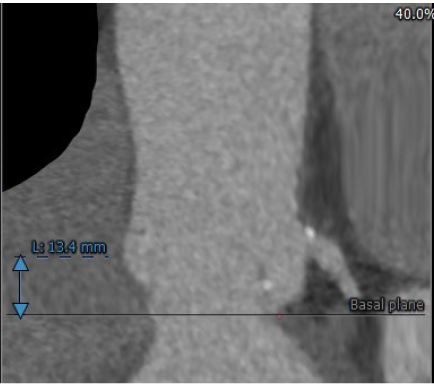

冠脉高度尚可。左冠高度:13.4,右冠高度:20.6。心脏角度52